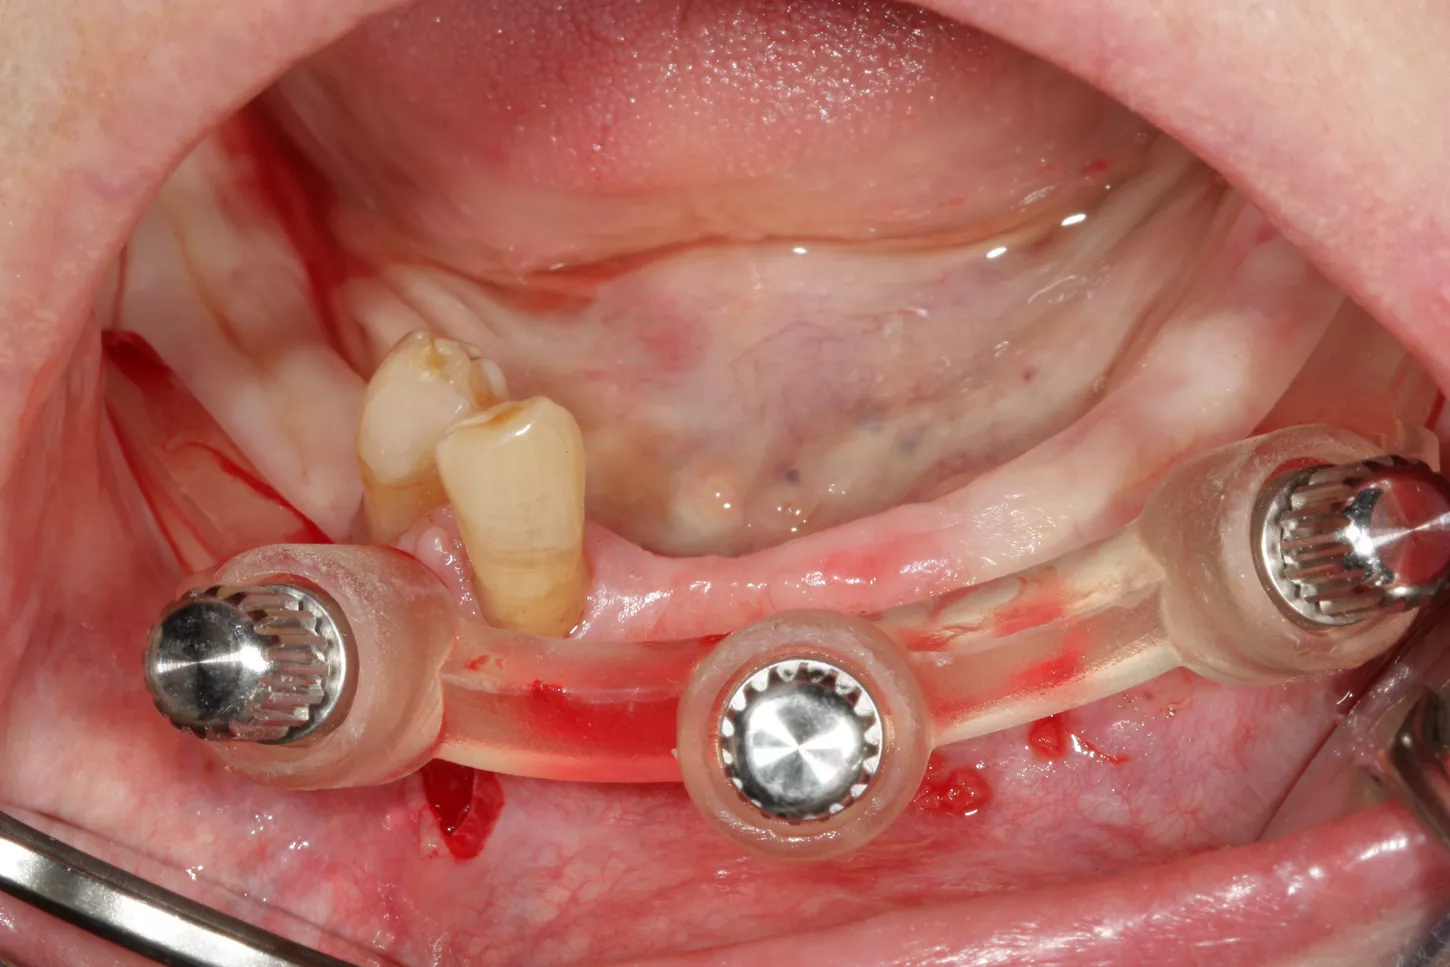

4. Maintenance of the Occlusal Vertical Dimension (OVD) for immediate restoration by temporary attachment of the positioning bar in occlusion by a stackable guide design (Priamond.de) and using the anchor pins included in the INTEGRAL kit.

5. Using the bar which stays in the mouth, we were able to position the actual drilling guide precisely despite the complete removal of the remaining teeth.